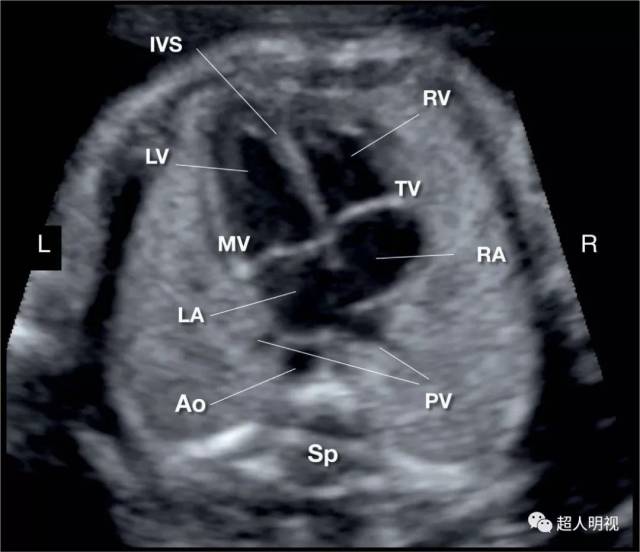

胎儿四腔心切面

心尖四腔心切面.la.左心房;lv.左心室;ra.右心房;rv.